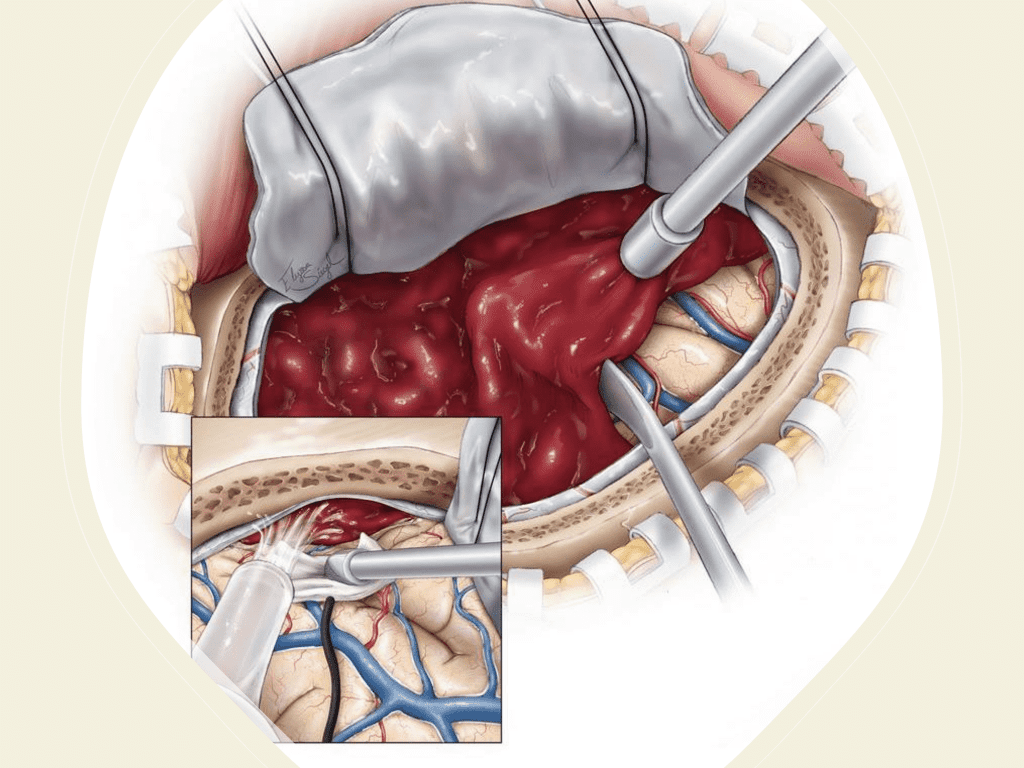

The treatment and management of cSDH remains controversial and has traditionally been treated either conservatively with observation and serial imaging in asymptomatic patients and smaller collections (without midline shift) or more aggressively with surgical evacuation in symptomatic patients or larger collections (with greater than 5 mm of midline shift). There is a variety of surgical options for cSDH treatment including twist-drill craniotomy (5-10 mm incision) with or without a subdural evacuating port system (SEPS), burr hole evacuation (silver dollar or up to 30mm incision) with or without drains, or craniotomy (>30 mm incision). Irrespective of the type of evacuation, cSDH surgical treatment continues to have high recurrence rates ranging from 5% to 37%, thereby subjecting these patients to repeat surgical interventions, hospital admissions, and the associated complications including peri-operative morbidity, diminished neurologic and functional status, and even mortality (5).

Figure 6. Surgical craniotomy for Subdural Hematoma. (https://www.neurosurgicalatlas.com/volumes/emergency-neurosurgery-and-trauma/traumatic-hematoma/acute-subdural-hematoma((c)2022, The Neurosurgical Atlas) (6).